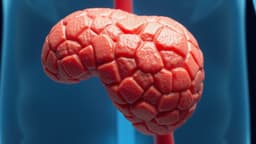

In a remarkable medical feat, doctors at MDM Hospital's Zanana Wing in Jodhpur successfully removed a massive 6kg uterine fibroid from a pregnant patient, saving both her and her unborn child. The 31-year-old woman, Payal from Ajmer, was admitted in June 2025 during her fourth month of pregnancy with severe abdominal pain and swelling.

Diagnostic imaging revealed a uterine fibroid of extraordinary size, measuring approximately 22 × 18 × 16 cm. Such large fibroids during pregnancy are exceedingly rare, impacting an estimated one in eight to ten lakh cases. Recognizing the life-threatening risks, the medical team opted for a complex myomectomy during the second trimester, a procedure that necessitated six units of blood transfusion.